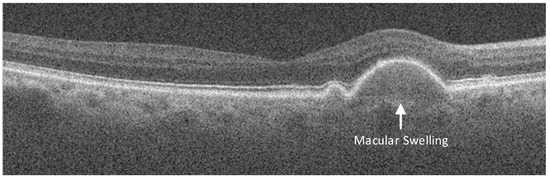

3.1. OCT Dataset